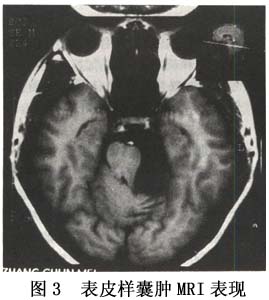

3.MRI MRI檢查對於診斷及發現顱後窩表皮樣囊腫,尤其是腦幹旁表皮樣囊腫優於CT。它能顯示其占位效應腫瘤範圍血管移位等。多數病例呈長T1和長T2,在T1加權像上呈低信號,T2加權像上為高信號,瘤質不均勻而致信號強度變化不定是其MRI特徵(圖2,3)。